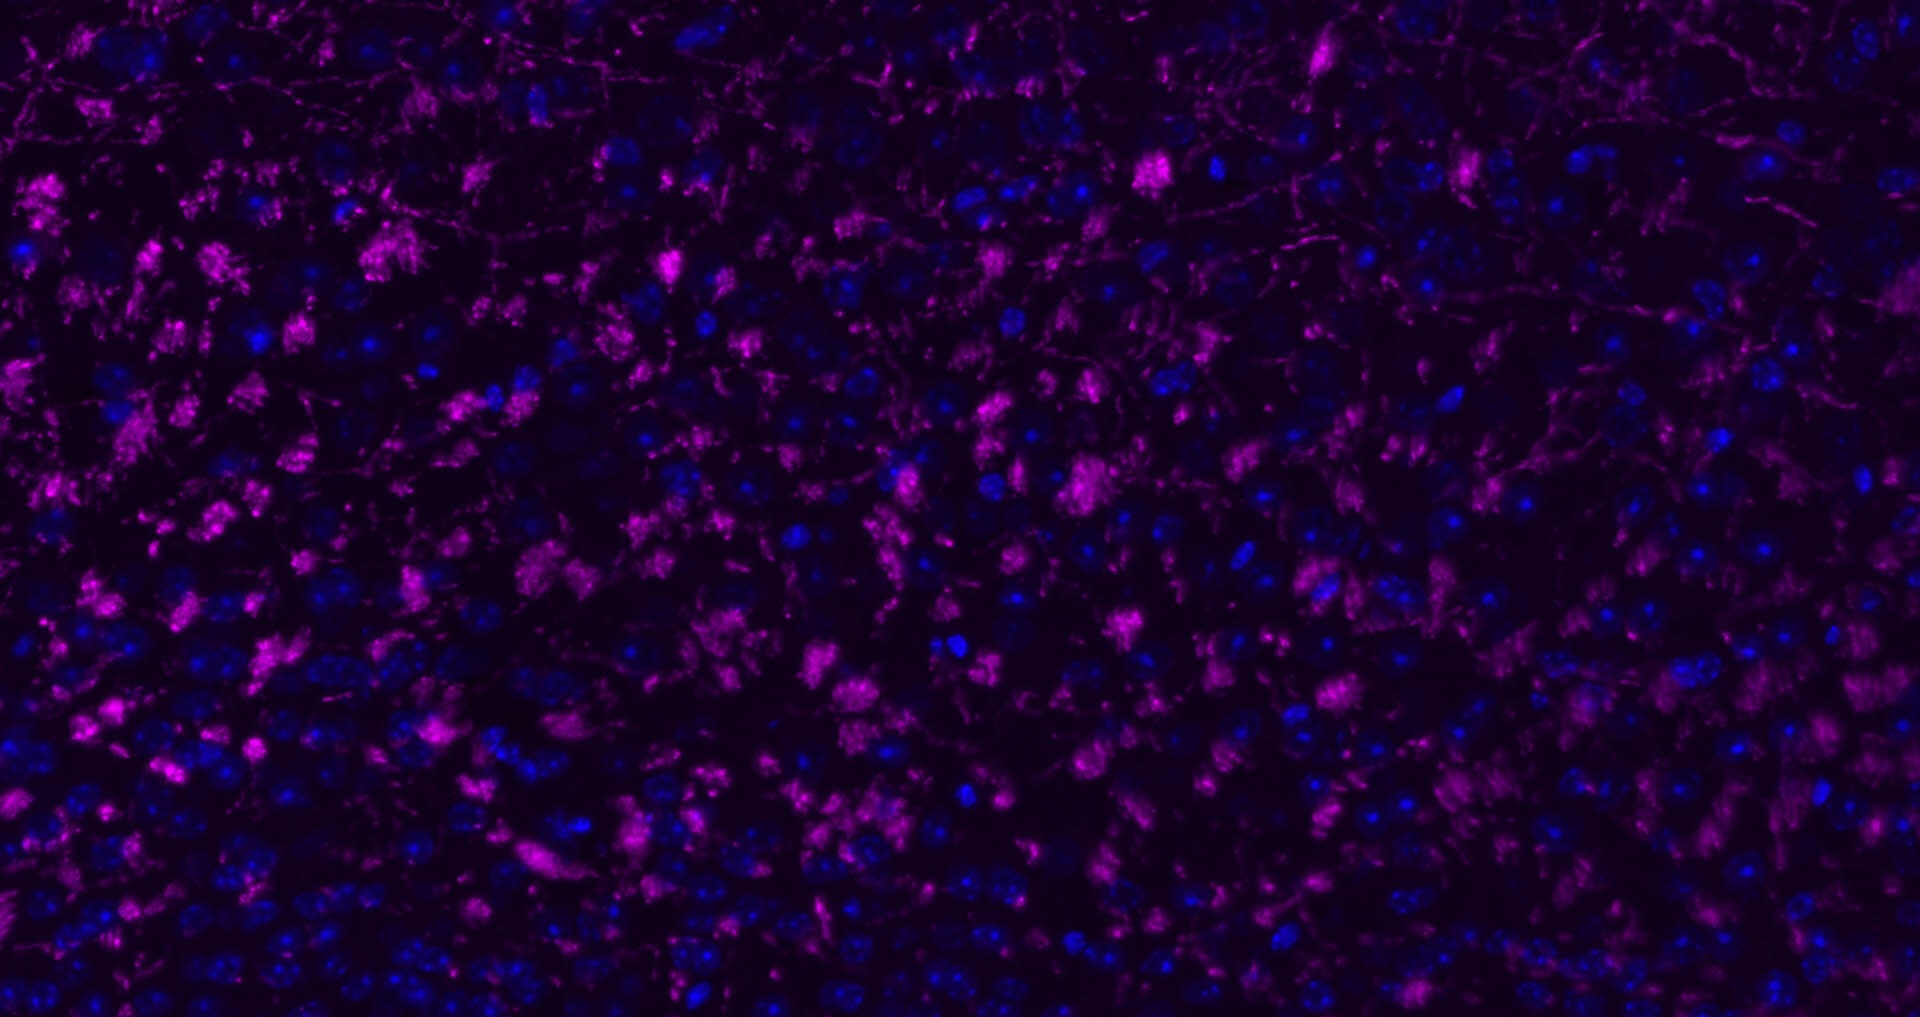

4. Paraformaldehyde-fixed, paraffin embedded (rat brain); Antigen retrieval by boiling in sodium citrate buffer (pH6.0) for 15 min; Block endogenous peroxidase by 3% hydrogen peroxide for 20 min; Blocking buffer (normal goat serum) at 37°C for 30 min; Antibody incubation with (MBP) Polyclonal Antibody, Unconjugated (TMAB-01110) at 1:200 overnight at 4°C, followed by operating according to SP Kit (Rabbit) instructionsand DAB staining.

5. Paraformaldehyde-fixed, paraffin embedded (mouse brain); Antigen retrieval by boiling in sodium citrate buffer (pH6.0) for 15 min; Block endogenous peroxidase by 3% hydrogen peroxide for 20 min; Blocking buffer (normal goat serum) at 37°C for 30 min; Antibody incubation with (MBP) Polyclonal Antibody, Unconjugated (TMAB-01110) at 1:200 overnight at 4°C, followed by operating according to SP Kit (Rabbit) instructionsand DAB staining.